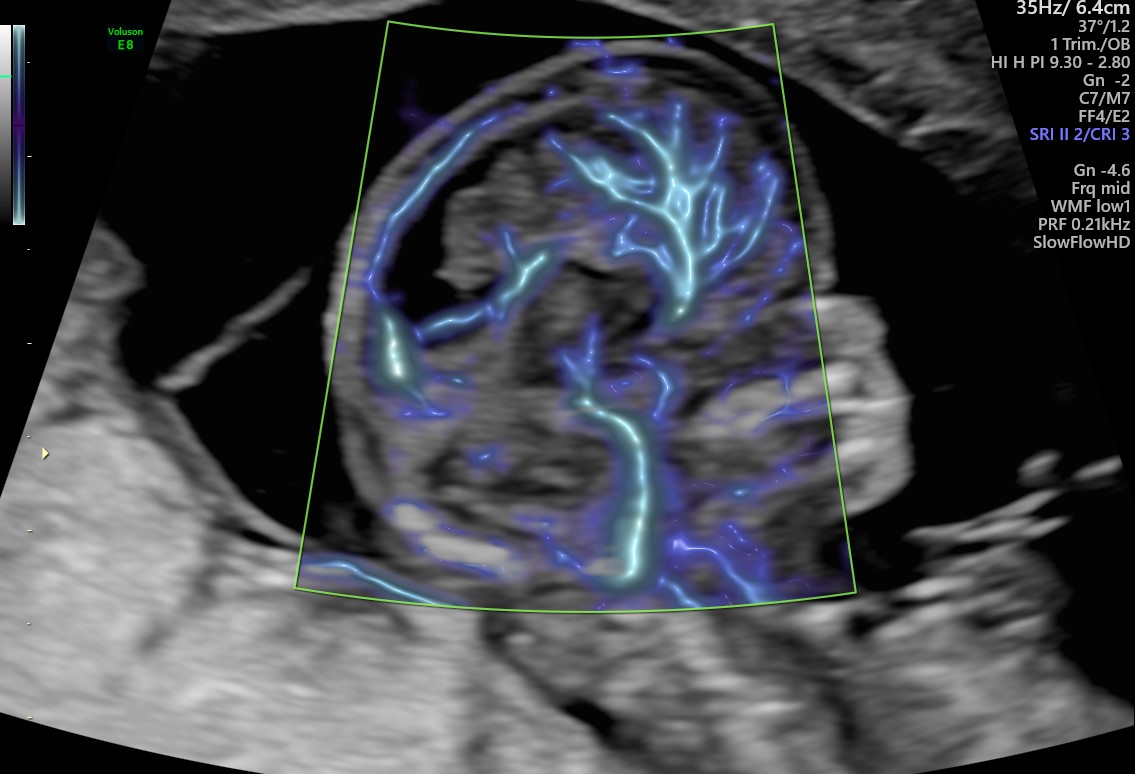

SlowflowHDTM

Adatto allo studio del micro-circolo, SlowflowHD può essere utilizzato anche in combinazione con Radiantflow ed utilizza entrambe le mappe Doppler mono e Bi-Direzionali a seconda delle vostre esigenze.

Applicazioni cliniche principali: cervello fetale, reni, placenta e studi avanzati di ginecologia